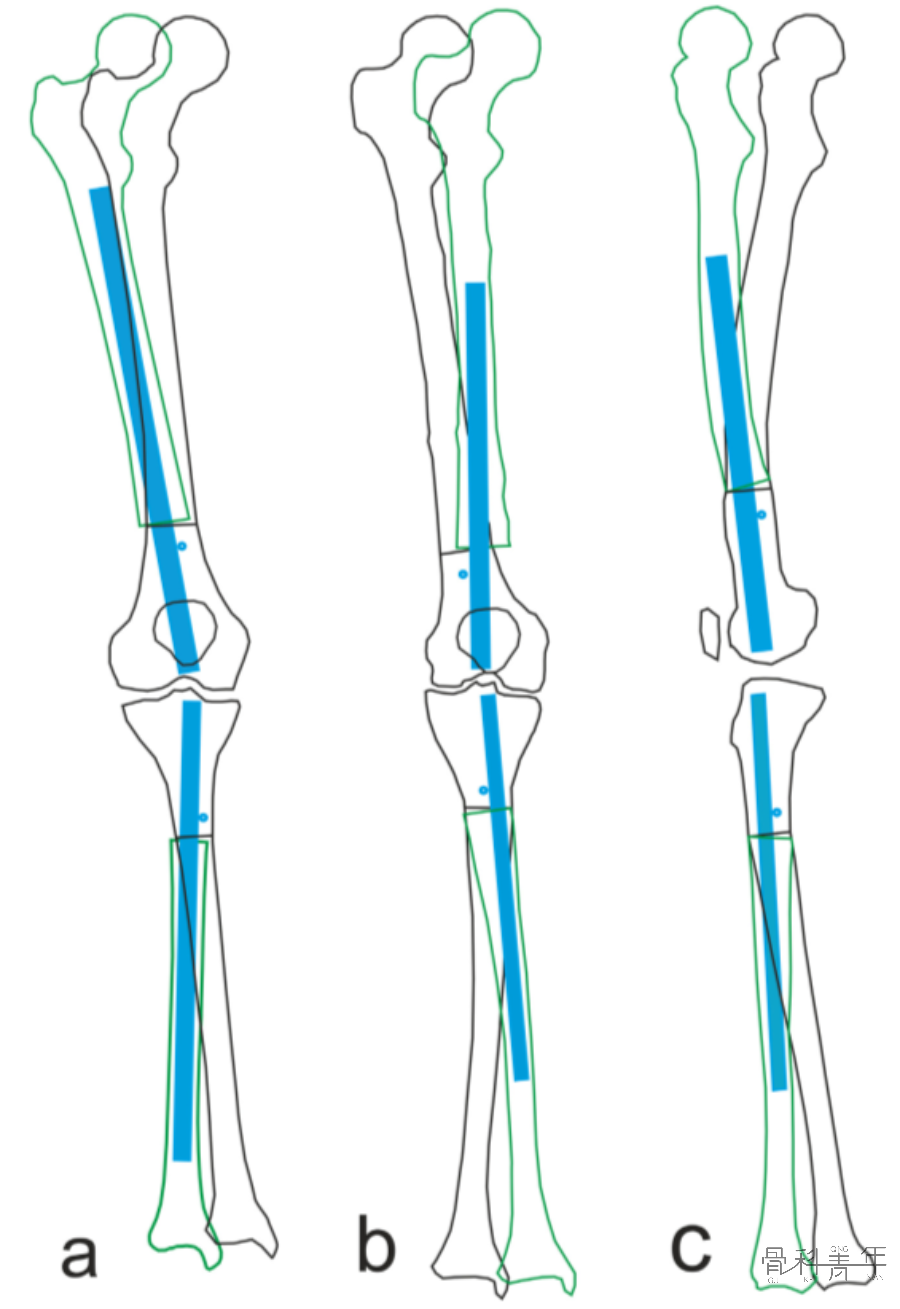

除了在骨折治疗中调整骨折的对线外,在下肢畸形矫正中,通过阻挡钉矫正髓内钉的位置,以达到同期手术完成多平面对线,也可取得良好效果。

为了矫正股骨力线,在干骺端横行截骨(a横行虚线)后,截骨远端移位,此时髓内钉置入后应为偏心方可维持矫形,为了获得髓内钉位置,需要置入阻挡钉(b)。

依上述理论及病例解析,不难发现,无论对于股骨或胫骨,无论畸形方向,均可以通过阻挡钉来位置髓内钉位置。各部位及各畸形状况下阻挡钉置入位置如下图: